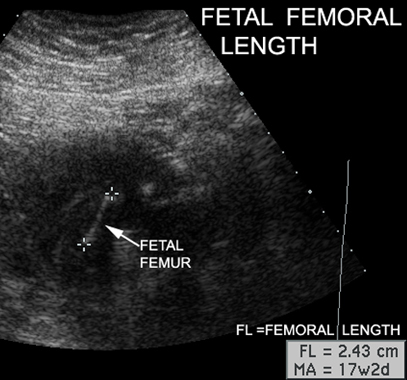

Items Measured by Ultrasound |

Measurements |